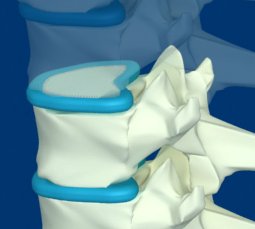

Межпозвонковый диск представляет собой плоскую прокладку круглой формы, расположенную между двумя соседними позвонками.

Межпозвонковый диск имеет сложное строение. В центре находится пульпозное ядро, которое имеет упругие свойства и служит амортизатором вертикальной нагрузки.

Вокруг ядра располагается многослойное фиброзное кольцо, которое удерживает ядро в центре и препятствует сдвиганию позвонков в сторону относительно друг друга.